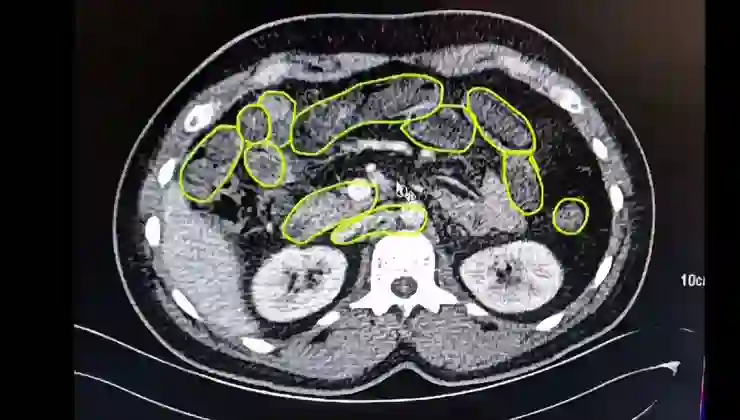

Röntgen ve ultrason sonrası kontrollerde 3 şüphelinin midesinde uyuşturucu madde olduğu belirlendi.

Şüphelilerin yuttukları uyuşturucuları kente sokmaya çalıştıkları tespit edildi. Kapsüller, sağlık ekibinin müdahalesiyle çıkarıldı. Taburcu edilen şüpheliler, İlçe Jandarma Komutanlığı’na götürüldü.